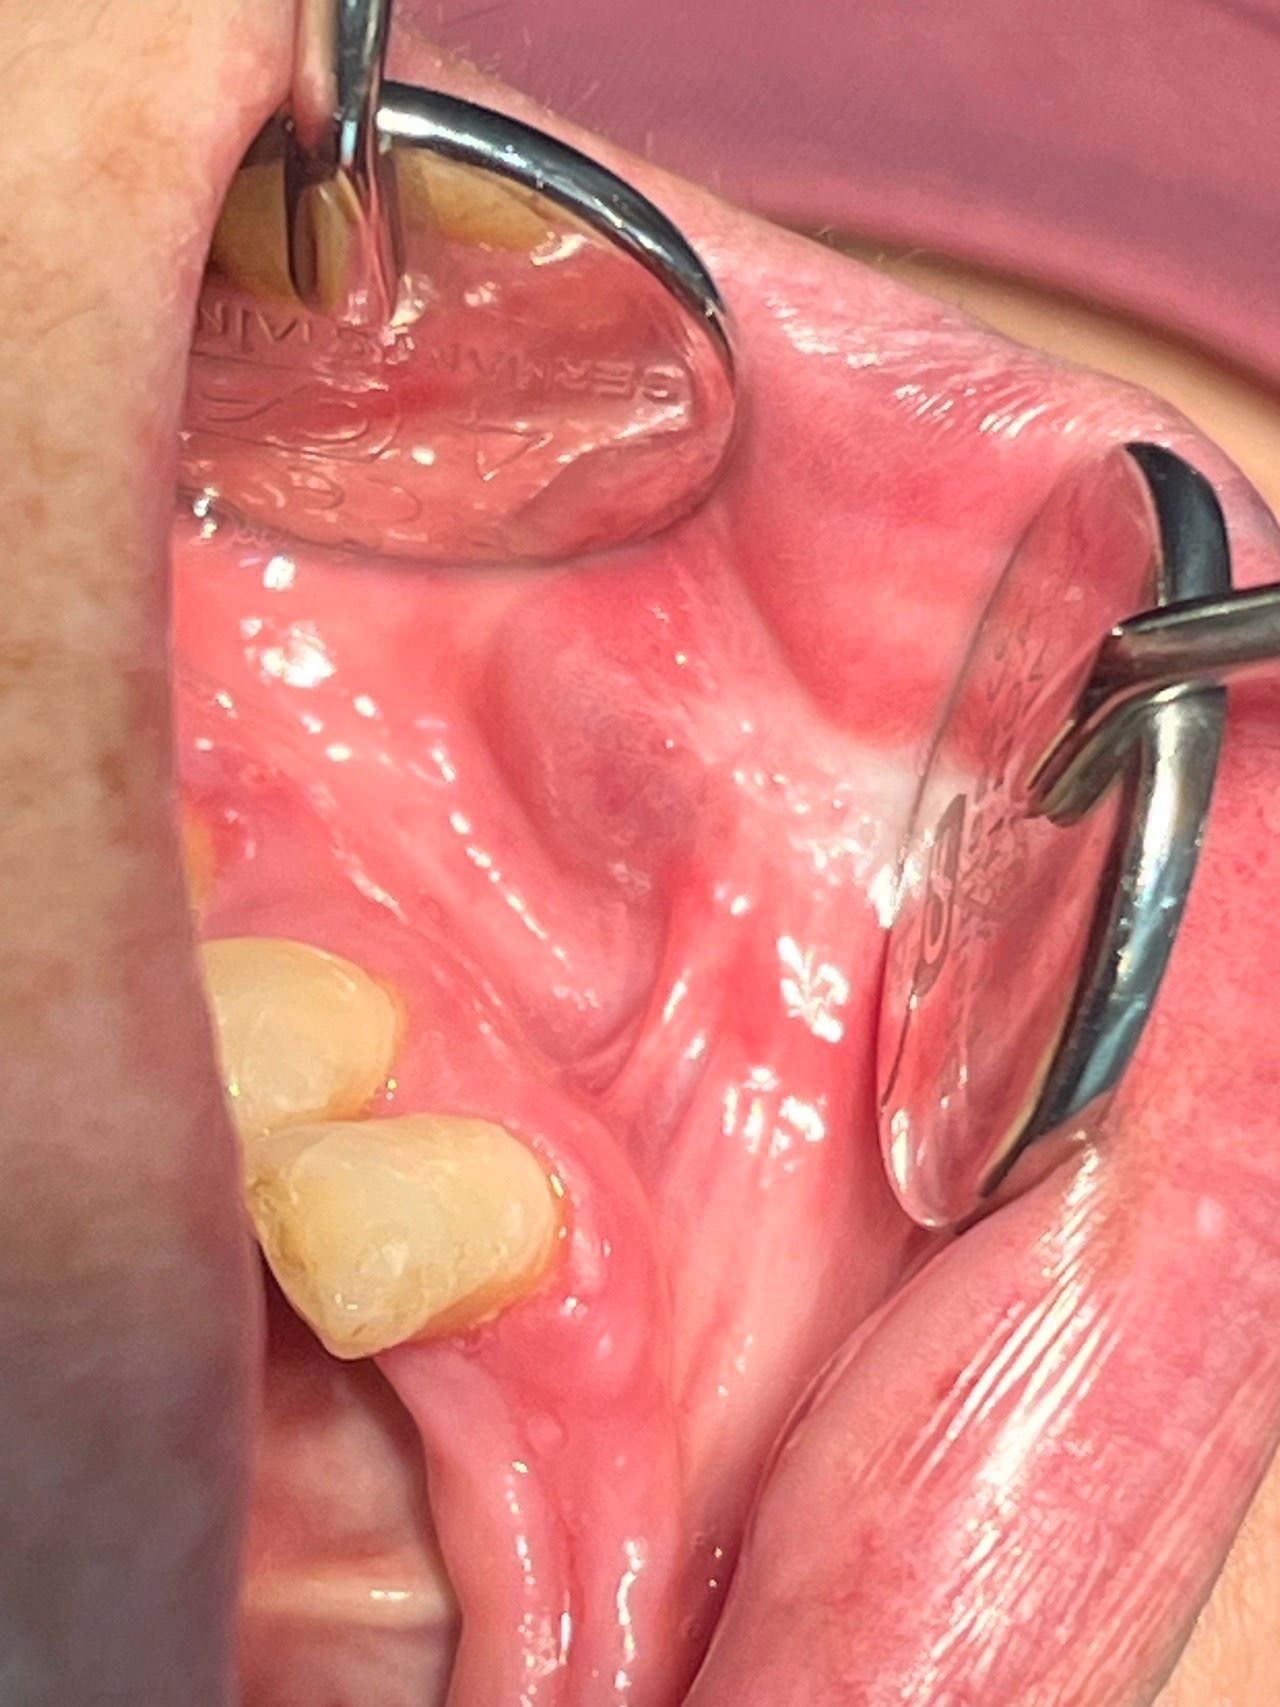

一位67歲女性,因牙周治療期間意外發現左下唇無症狀腫塊,前來台北長庚醫院口腔外科求診。該腫塊呈藍紫色,直徑約兩公分半,造成左下臉部輕度腫脹變形,且已存在20年。臨床檢查顯示無脈動感,按壓呈缺血色變,診斷為良性口腔血管異常(BOVA)。醫療團隊採用冷凍槍進行治療(cryogun cryotherapy),每次包含兩輪冷凍與解凍循環。三次療程後病灶明顯縮小,最終完全消失。6個月追蹤期間未見復發,證實冷凍治療可安全有效根除BOVA,亦可避免傳統手術的出血與疤痕風險。

病灶多呈現紅紫或藍紫色外觀

良性口腔血管病變是一種常見的口腔黏膜疾病,估計約每百位頭頸部病患中就有6至7位罹患,發生族群不限年齡與性別。病灶多呈現紅紫或藍紫色外觀,常見於舌、頰黏膜、口底等部位,不僅影響美觀與進食,亦可能出現出血、疼痛等臨床症狀。嚴重者可能因自發性出血引發急性併發症,甚至危及生命。